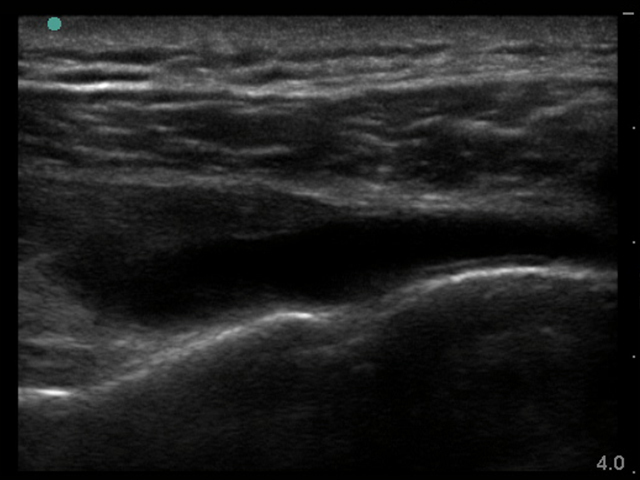

Image - Épaule postérieure, Épanchement de l'articulation